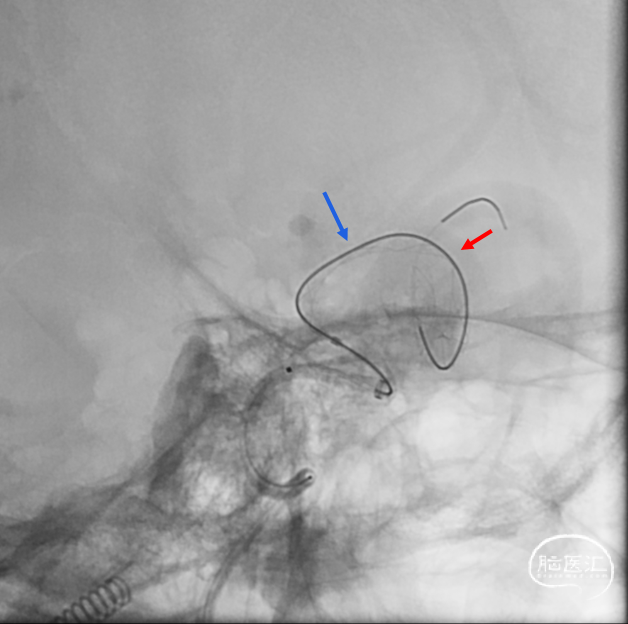

支架打开不良

支架重新打开良好